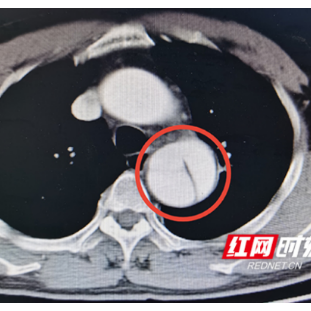

检查结果中被撕成两瓣的主动脉

邓先生入院后,测量血压180/90mmHg,经CTA(CT血管造影)等检查,明确诊断为主动脉夹层B型,主动脉被撕开成两半,随时有破裂大出血死亡风险,需手术治疗。经完善手术准备,邓先生接受了全麻下主动脉夹层腔内隔绝术,术中用一枚支架修复主动脉的破口,拆除了随时可能爆炸的“炸弹”。术后邓先生经过康复,已于今日出院。邓先生的家人表示:“以前没听说过血管夹层这种病,没想到普通的一个咳嗽还可能是要命的病,多亏当时医生提醒,才得以及时救治。”